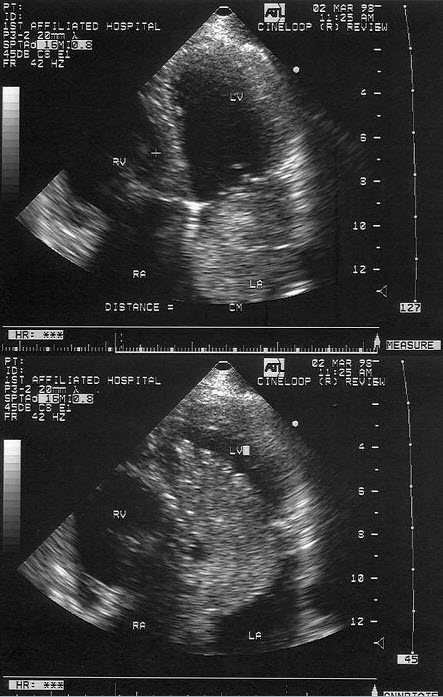

6、单项选择题

该病例最有可能诊断是()

A.左房黏液瘤

B.左房巨大血栓

C.左房恶性肿瘤

D.左房转移瘤

E.以上都不是

E.假性动脉瘤

45、单项选择题

如图,初步超声诊断为()